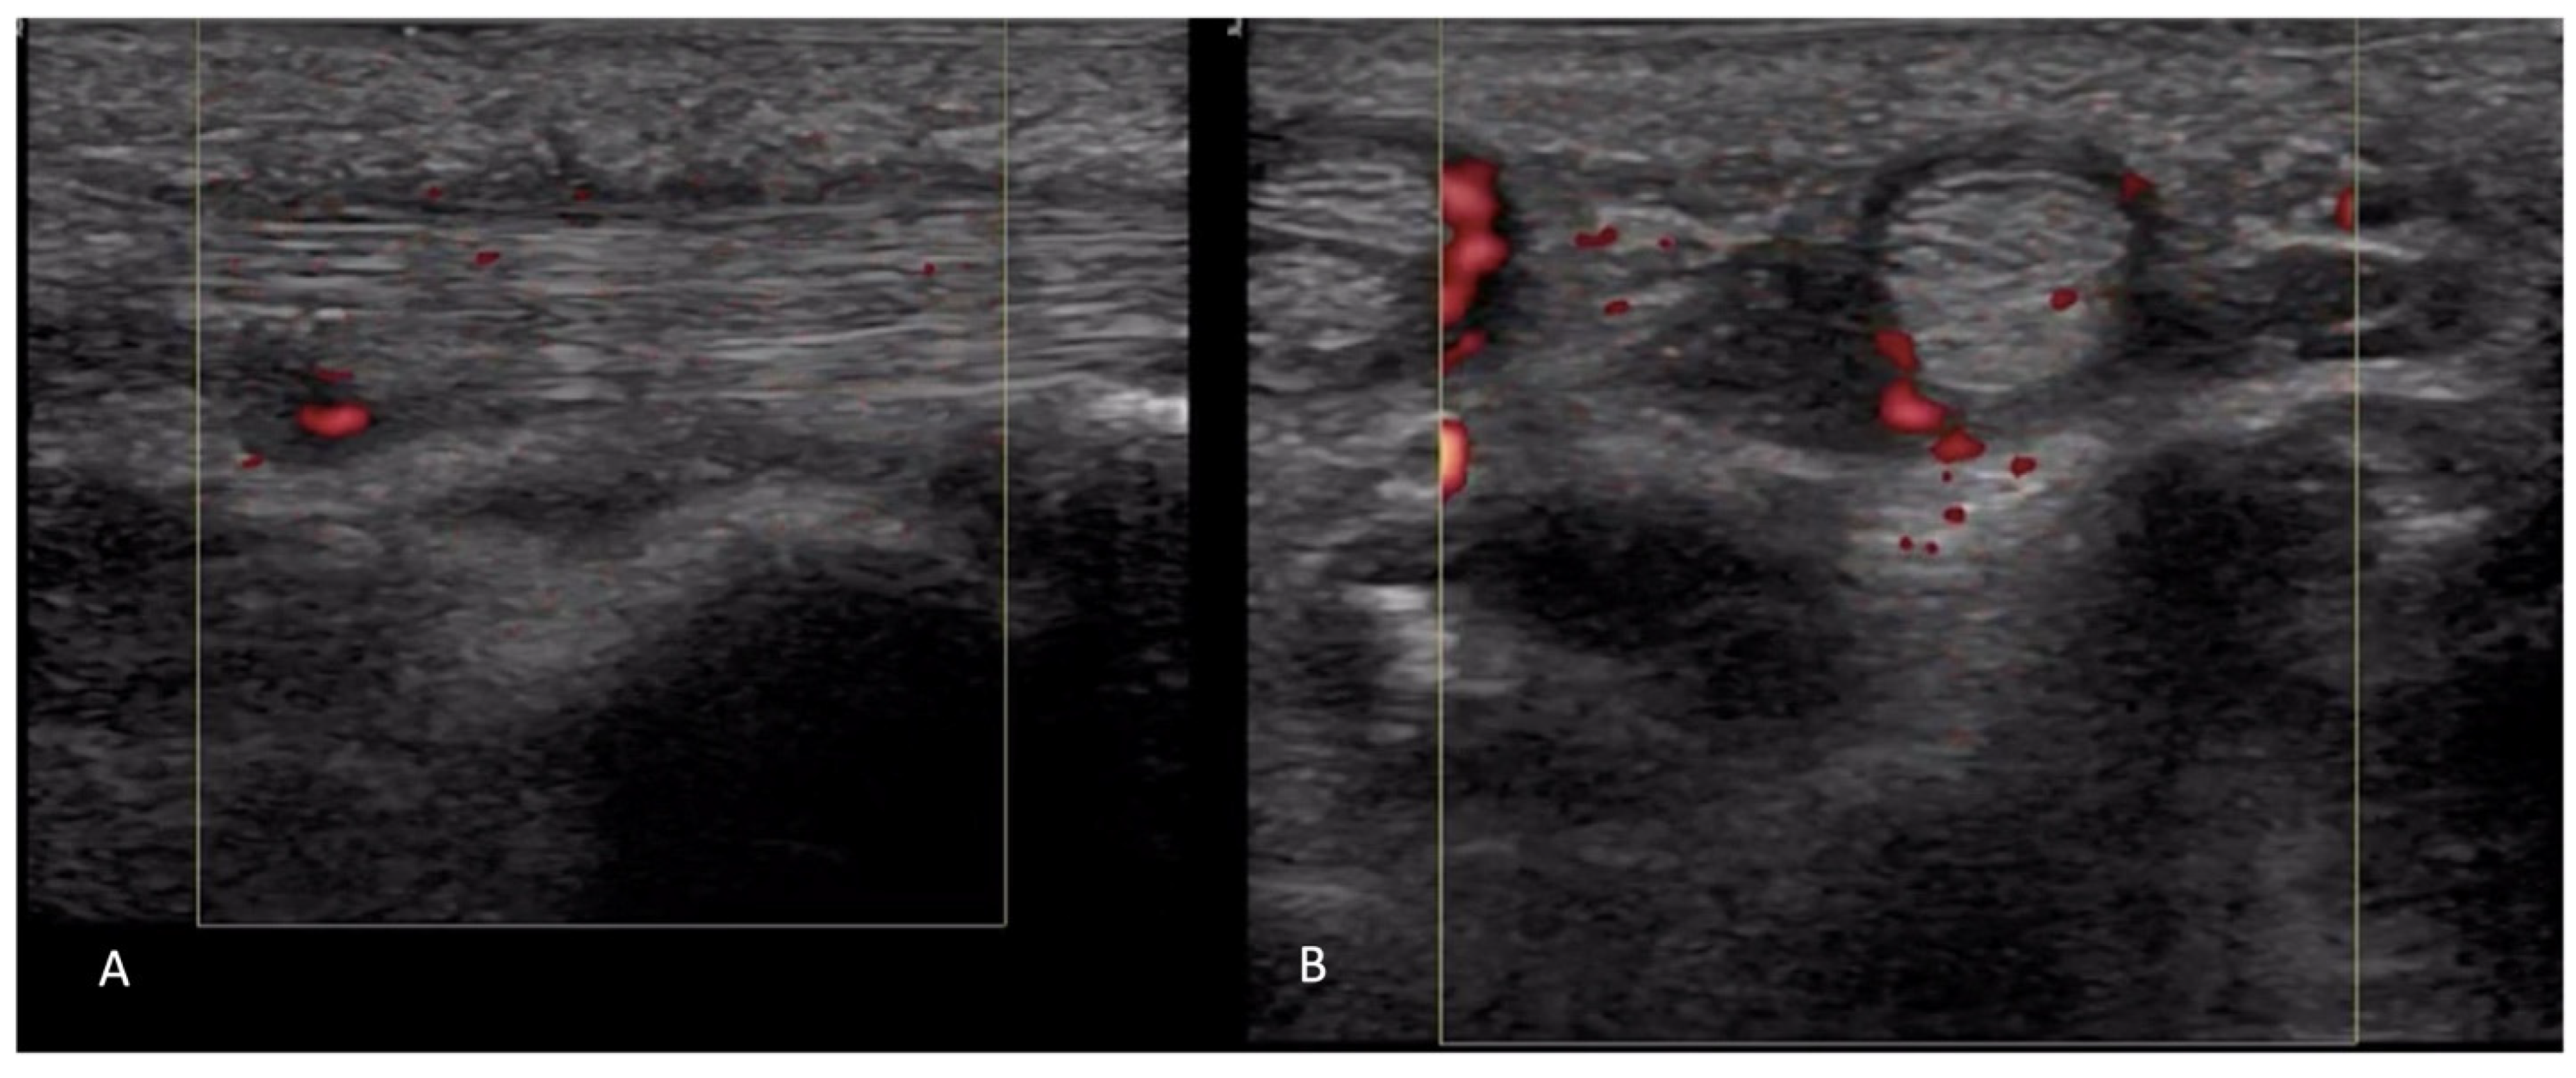

2.4. Vascular Pathology

- Lescoat, A.; Coiffier, G.; Rouil, A.; Droitcourt, C.; Cazalets, C.; de Carlan, M.; Perdriger, A.; Jégo, P. Vascular Evaluation of the Hand by Power Doppler Ultrasonography and New Predictive Markers of Ischemic Digital Ulcers in Systemic Sclerosis: Results of a Prospective Pilot Study. Arthritis Care Res. 2017, 69, 543–551. [Google Scholar] [CrossRef] [PubMed]